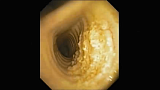

Макроскопически обнаруживаются плотные белесоватые узелки с неправильными очертаниями, выступающие над поверхностью слизистой, диаметром 1-3 мм (характерная картина «металлической тёрки»), располагающиеся исключительно в хрящевой части трахеи и никогда в мембранозной. Такая избирательная локализация патологических изменений характерна только для остеохондропластической трахеобронхопатии и не наблюдается при других заболеваниях дыхательных путей. Эти возвышающиеся узелки могут иногда сливаться в тяжи.